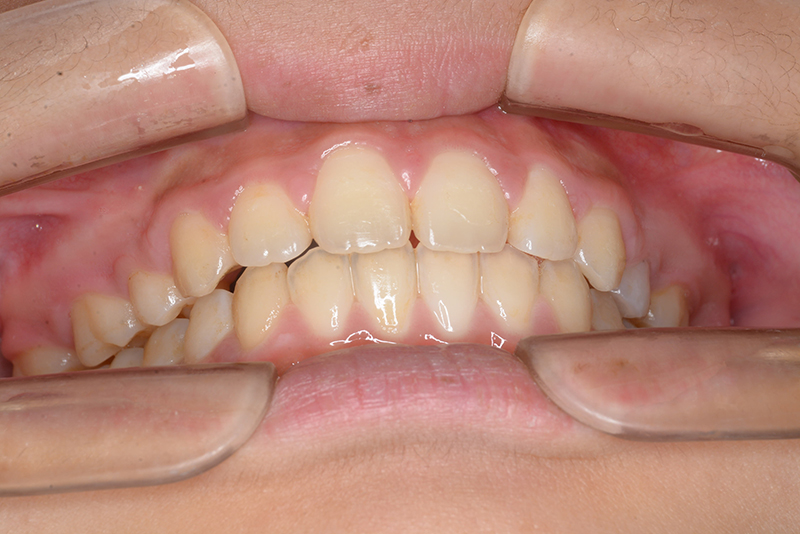

初診時

FP・IOP

顔貌所見 上唇の突出が著しく閉唇時には口腔周囲筋の緊張感が認められ、安寧時には上顎前歯が露出し下唇はその内側に入っており口唇間隙も大きくなっていた。

口腔内所見 大臼歯関係は右側がエンドオンのclassⅡ、左側がfull classⅡ。 上顎正中は下顎正中に対して僅かに右側偏位しており、上顎前歯は大きく唇側傾斜しover jetが11.0mmと上突咬合を呈していた。また下顎歯列の緩やかなスピーカーブのため過蓋咬合(over biteは5.0mm)となっていた。